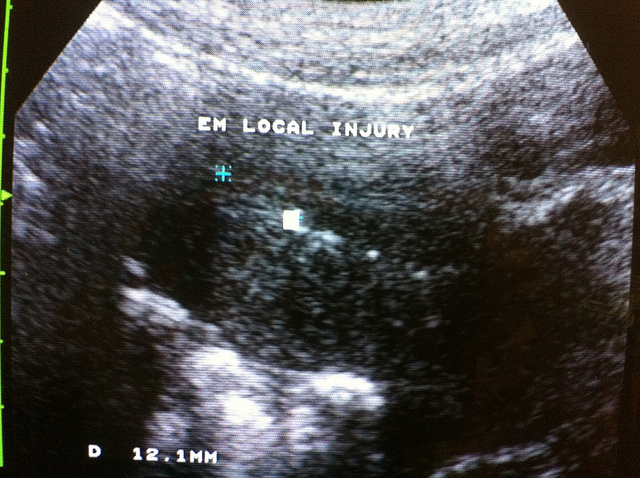

透過超音波抽取術 巧克力囊腫復發率低

鉅亨網新聞中心(來源:健康醫療網)2012-10-14 06:26

在台灣,巧克力囊...